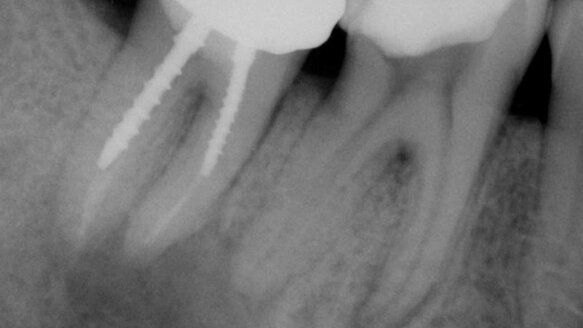

Le cone beam m'aide à éviter d'éventuelles surprises inopportunes, pendant le traitement. Par exemple, un patient m'a consulté, avec un gonflement persistant. Bien que l'image postopératoire en 2D montre une guérison (figures 1a et 1b), le cone beam a montré une zone d'infection très étendue, jusqu'au nerf dentaire inférieur, avec une destruction importante de l'os cortical (figure 2). Cette information est indispensable, en préopératoire.

Chez un autre patient, qu'il souffrait d'une douleur intense à une dent restaurée, avec une très grande raréfaction périapicale, j'ai décidé de pratiquer une résection apicale pour apporter un soulagement immédiat. Sur une radiographie 2D, tout paraissait simple (figure 3) mais, parce que le problème était sur une dent postérieure, pour des raisons de sécurité, j'ai décidé d'effectuer un cone beam.

La vue 3D a montré que l'affection avait pénétré si profondément, en lingual (figure 4) qu'une couche très épaisse d'os cortical a dû être retirée, et le positionnement du nerf alvéolaire était si haut qu'une paresthésie pouvait en résulter.